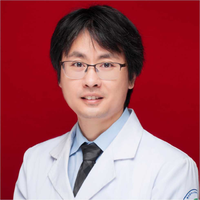

章述军

副主任医师

重医大附一院

感染病科